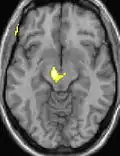

Positron emission tomography (PET) shows brain areas being activated during pain.

Voxel-based morphometry shows brain area structural differences.

Positron emission tomography (PET) scans indicate the brain areas which are activated during attack only, compared to pain free periods. These pictures show brain areas that are active during pain in yellow/orange color (called "pain matrix"). The area in the center (in all three views) is activated only during cluster headaches. The bottom row voxel-based morphometry shows structural brain differences between individuals with and without CH; only a portion of the hypothalamus is different.[36]